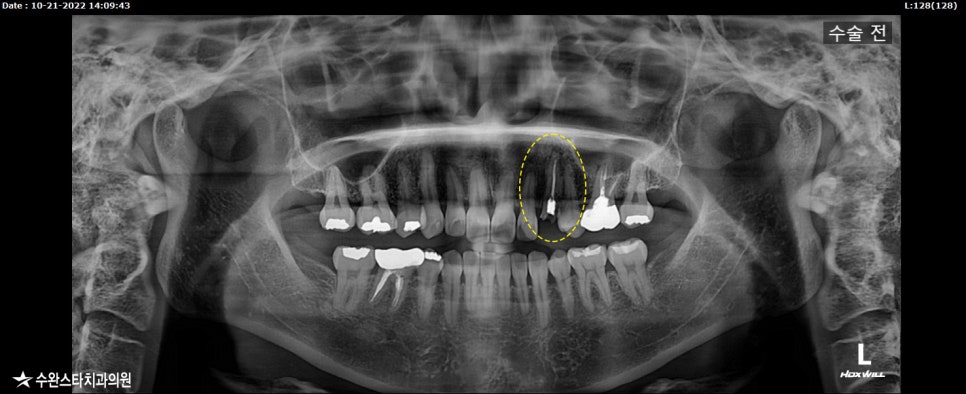

먼저 치주 상태를 확인하기 위하여

엑스레이 촬영하였습니다.

발치 전 엑스레이, 40대 여성 (2022.04)

엑스레이 표시된 부분을 보면

치아가 부러진 모습과

신경치료 했던 치아 뿌리 쪽으로

염증이 다시 생긴 걸 확인 할 수 있습니다.